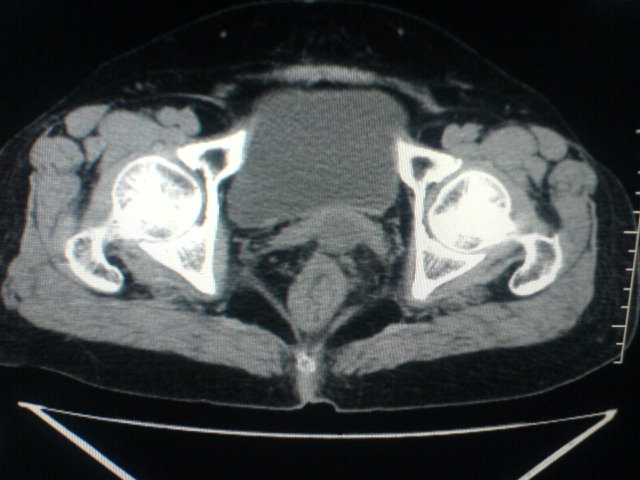

患者为老年女性,肿块最大层面不是位于宫颈,但宫颈偏后方有一囊状低密度影,肿块主要位于乙状结肠及直肠,所以考虑乙状结肠及直肠癌浸犯宫颈可能性大。

患者女性60岁 病史不详

宫颈癌侵犯直肠可能

考虑子宫内膜癌浸犯直肠。

考虑直肠癌侵及宫颈可能;建议增强扫描。

支持考虑宫颈癌上下前后通吃

考虑:直肠及乙状结肠癌侵及宫颈,囊性转移(假性粘液瘤)

支持宫颈癌侵犯直肠。

考虑直肠及乙状结肠癌侵犯邻近结构。